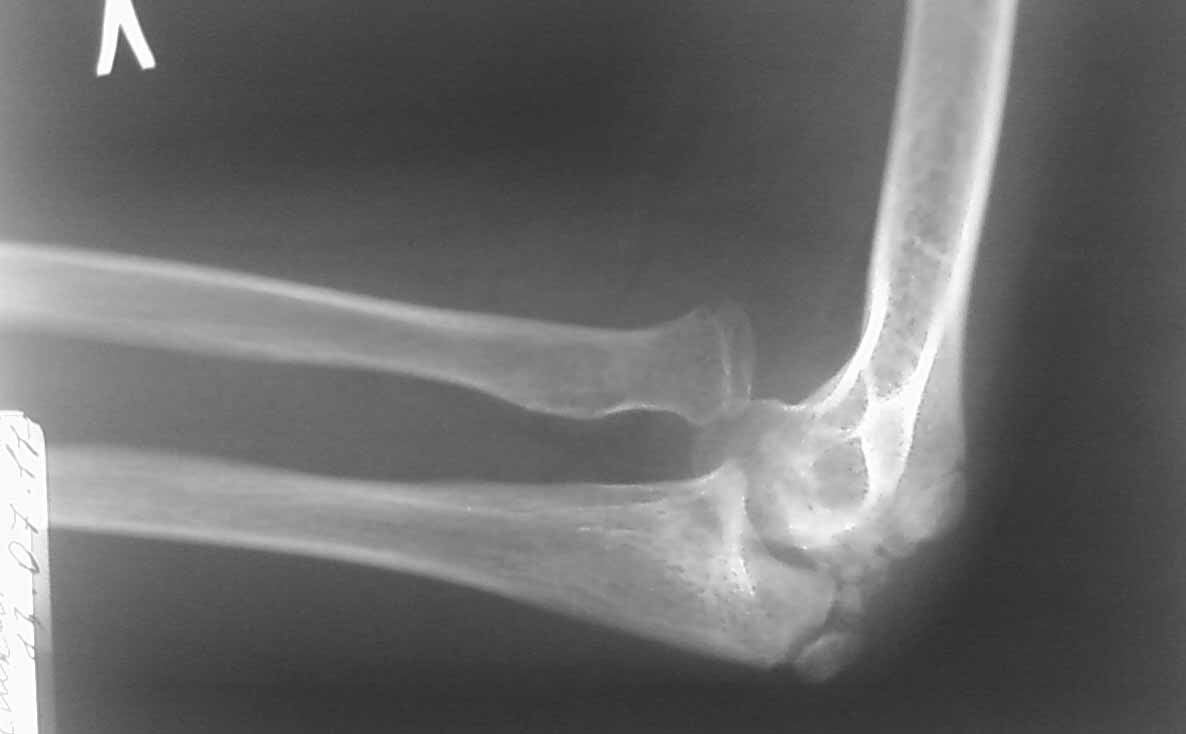

Снимок в боковой проекции не получилось сразу отправить.

Ответ собственно на все вопросы на боковой рентгенограмме: вывих лучевой кости. Либо перенесенный недиагносцированный-нелеченный Монтедж (повреждение Монтаджа: вывих лучевой кости с переломом локтевой кости). Более редкий вариант (скорее всего выявили бы раньше - врожденный вывих лучевой кости. Но честно говоря патология крайне редкая, да и не очень похоже.

Присмотрелся к боковой рентгенограмме сейчас... А можно повторить снимки в более стандартных укладках? А то складывается ощущение полного вывиха костей предплечья... Или это шутка укладки... Все-таки 7 лет жить с вывихом в локтевом суставе как-то нонсенс... Или все совсем запущено и предыдущий пост отменяется.

Клинически: отмечается вальгусная деформация локтевого сустава 32º, передневнутренний вывих головки лучевой кости. Разгибание 175º, сгибание 82º.

На рентгенограмме. Нарушение пропорциональности дистальных структур плечевой кости не отмечается. Объемная деформация головки лучевой кости не визуализируется, отмечается передневнутренний вывих головки лучевой кости. Отмечается нарушение сферичности локтевой вырезки, объемный дефицит суставной поверхности, который привел к объемному конфликту в плечелоктевом суставе, став причиной ограничения сгибания. Гипертрофия венечного отростка, увеличение ширины локтевого отростка в боковой проекции. Все эти изменения свидетельствуют о перенесенном переломе в области локтевого отростка.